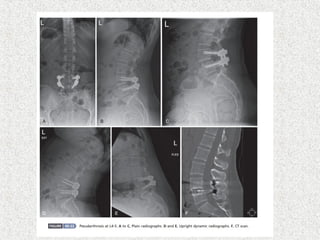

 Most diagnostic

 Persistent lucent line at the fusion site

 Visible motion on dynamic radiograph

Slip angle >30& lumbosacral angle >10 have predictive value for progression